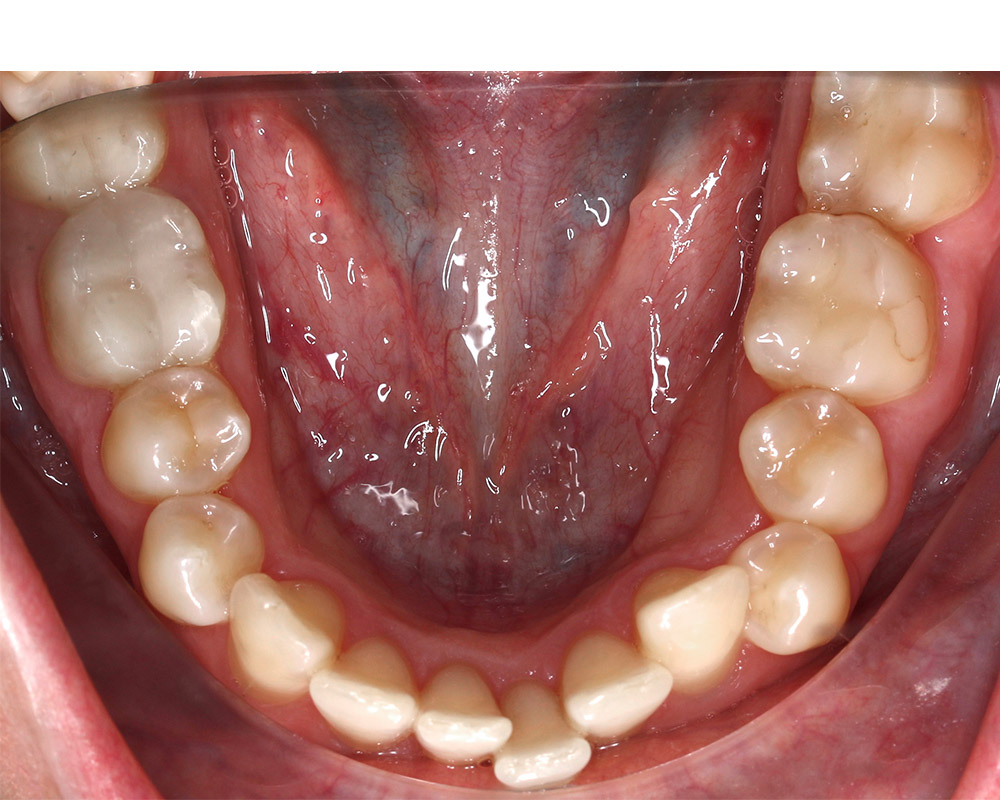

Кейс 13

Булгач (Мочалова) Галина Игоревна

Количество кап ВЧ 19

Количество кап НЧ 24

ДО

ПОСЛЕ